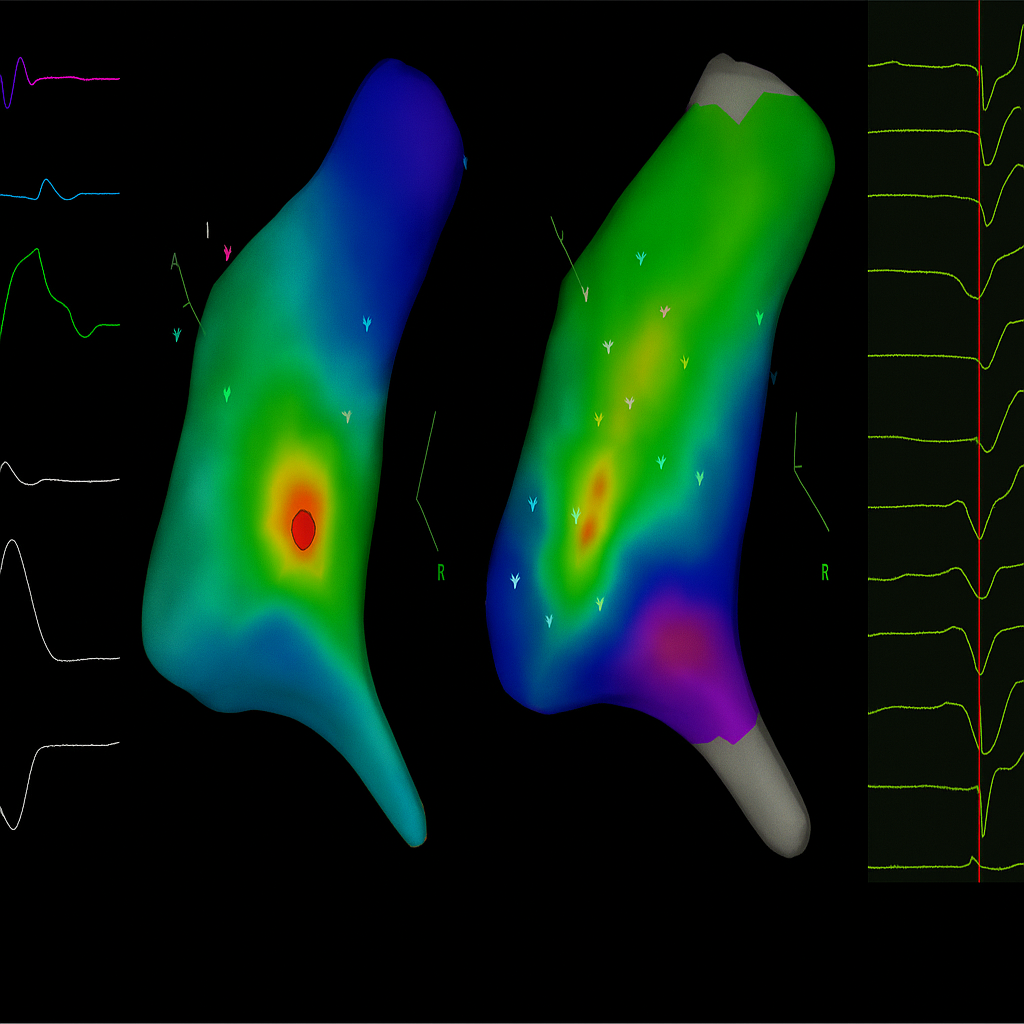

• Bu kateterlerle kalbin elektriksel haritası çıkarılır, VES’in kaynağı bulunur.

• Sorunlu noktaya enerji verilerek o bölgenin erken atım üretmesi engellenir.